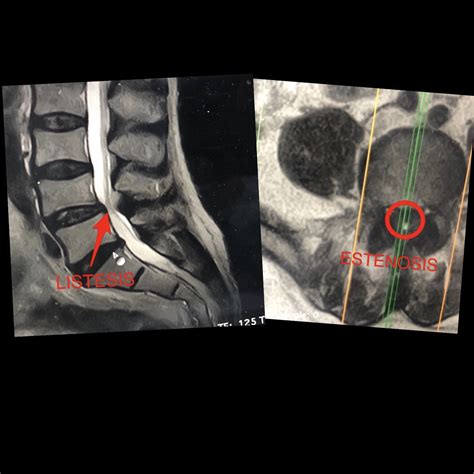

WebGRADO 1: MENOR – Normalmente siguen sin sentir ningún dolor ni molestia. El desgaste de la articulación es muy leve. GRADO 2: LEVE – Aquí hay un mayor crecimiento del. WebEl médico diagnostica el grado de escoliosis a través de una radiografía. Curvatura leve: cuando la escoliosis es de 20 grados o no los supera. Curvatura. WebLa estenosis lumbar es la disminución del volumen del canal raquídeo y/o de las foraminas que puede comprimir las raíces nerviosas. Existen múltiples causas para esta condición,. WebGran Invalidez: Es el mayor grado de incapacidad que puede sufrir una persona. Además de no poder realizar ninguna actividad laboral, también necesita la asistencia de otra. WebEstenosis de canal lumbar; Hernia discal lumbar; Fractura vertebral; Escoliosis; Lumbalgia. Lumbalgia por dolor discogénico; Lumbalgia por dolor facetario;. WebClasificación: 0-20 % limitación funcional mínima, 20 %-40 % limitación funcional moderada, 40 %-60 % limitación funcional intensa, 60 %-80 % discapacidad, por encima de 80 %. WebExisten cinco grados de discapacidad: grado 1 (discapacidad nula), grado 2 (discapacidad leve), grado 3 (discapacidad moderada), grado 4 (discapacidad grave) y grado 5 (muy.